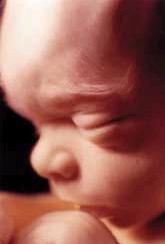

Хаскелл принес ультразвуковой зонд и разместил его сверху, чтобы видеть ребенка. На экране УЗИ было видно, как бьется сердце ребенка. Глядя на экран, доктор ввел клещи, ухватил ребенка за ноги и начал вытаскивать через родный канал. Затем вытащил ручки и все тельце до самой шеи; внутри оставалась одна только голова. Тельце ребенка двигалось, маленькие пальчики заплетались. Ребенок махал ножками. Доктор Хаскелл взял ножницы и ввел их внутрь, пробивая головку ребенка сзади. Затем вложил в отверстие трубку прибора, которым высосал мозг малыша. Когда я это видела, меня чуть не вырвало...

Всю жизнь работая медсестрой, я никогда не пережила ничего подобного. Позже имел место еще один такой случай. Это был шестимесячный ребенок, а матери было более сорока. Ребенок был совсем здоровый и нормальный – просто она его не хотела. Врач провел такую же операцию, и я снова видела на экране бьющееся сердце. Этот ребенок был немного меньше, чем предыдущий, его тело было полностью сформировано. Мать даже не хотела на него посмотреть. Пришел ассистент, забрал и вынес ведро с детьми...

Я никогда не задумывалась над тем, насколько сформировано тело ребенка на шестом месяце беременности. Когда говорят «эмбрион» или «плод», многие думают, как и я раньше, что это какая-то бесформенная масса, какой-то слепок живых клеток. Происшедшее открыло мне глаза, и я уже никогда не буду относиться к аборту так, как прежде.